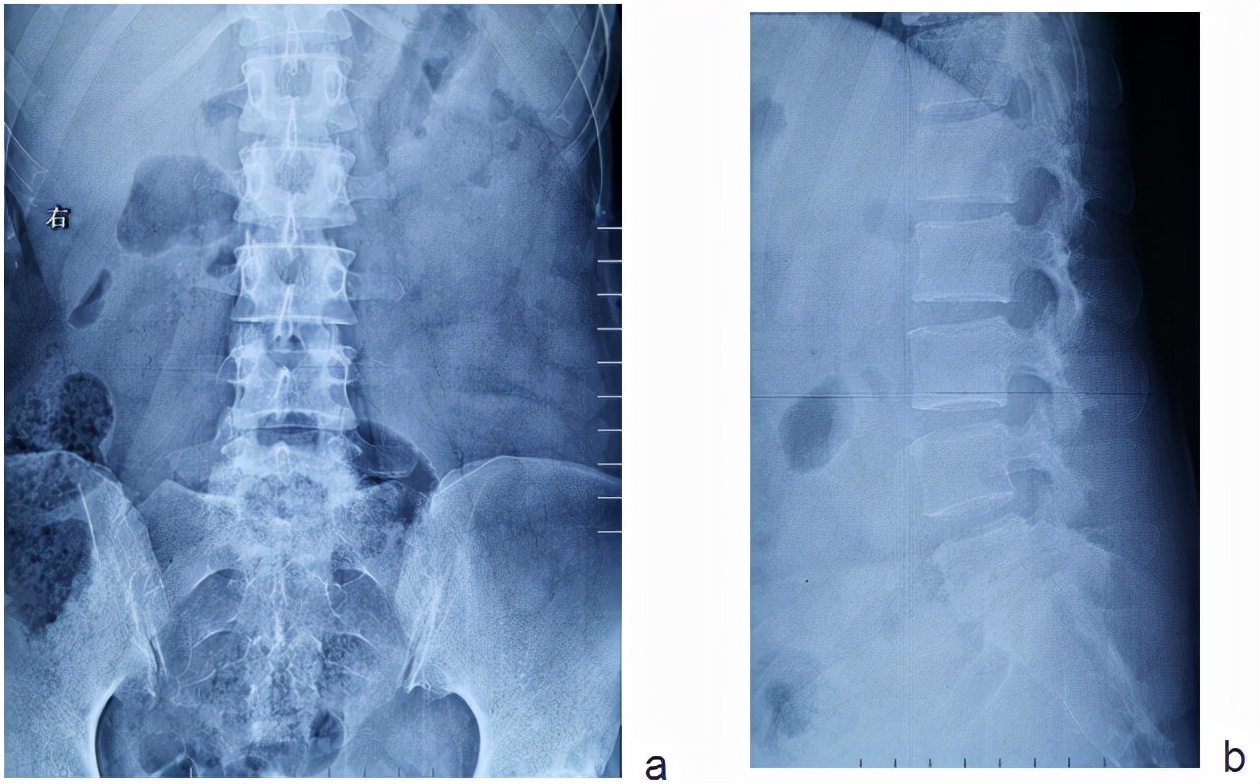

术前影像学表现

a、b示正侧位X线示腰5-骶1椎间隙塌陷,腰5椎体下缘和骶1椎体上缘可见骨折破坏。

c.CT示腰5-骶1椎间隙塌陷,腰5椎体下缘和骶1椎体上缘可见骨折破坏,伴有死骨的形成。